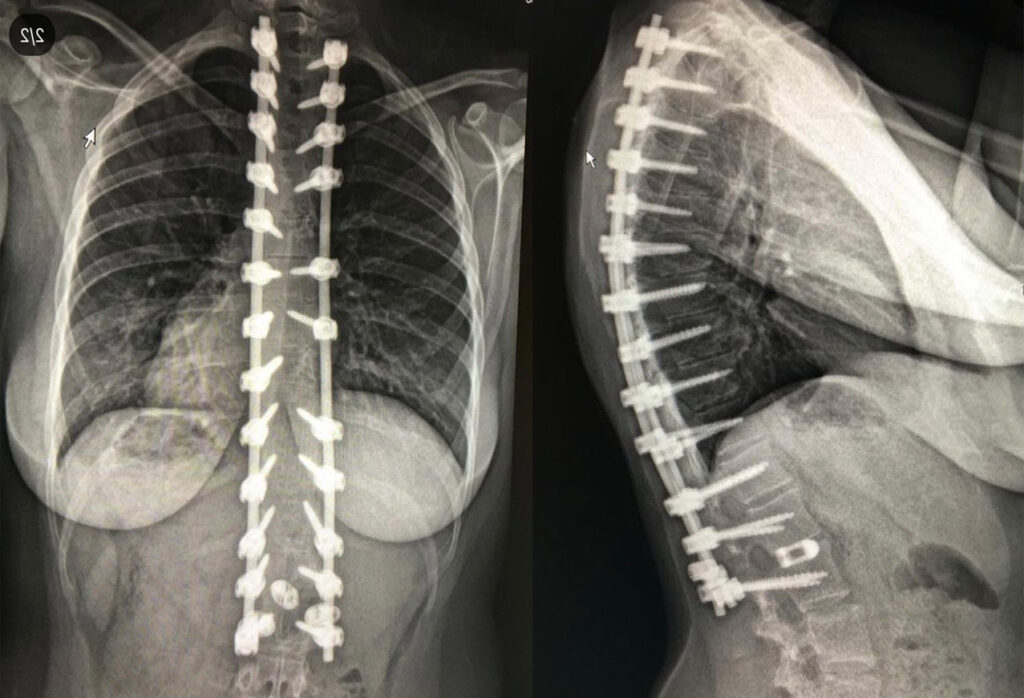

My name is Morgan and I found out I had scoliosis in 2013. I did months of physical therapy but that didn’t help so they scheduled me for surgery. I had my 1st surgery that same year, resulting in 2 rods and 24 screws from T2-L2. Recovery was hard and I had just lost my dad, but I got even stronger than I was before surgery. I went to the gym, played soccer, and ran a 5K. After about 3 ½ years, I had my 2nd surgery in 2017 to get two screws removed due to pain. I thought everything was going fine and wore a brace for 18 hours a day, but soon realized I would need another surgery. I had to have 2 more surgeries and was devastated, but determined to recover.

My surgeon was equipped to handle the risks associated with my surgeries and replaced one of my disks with an interbody fusion. I thought the pain and surgeries would never end, but eventually, they did. I then did months of physical therapy again and was able to graduate high school with honors and go back to work. It was a very hard journey but now I’m almost 5 years post-op from my last surgery and doing much better. I can relax and feel like my old self again. I still live with chronic pain but I’m trying everything I can to manage it. I’ve done physical therapy, massage therapy, steroid injections, medication, and braces. I lost my mom and stepdad during this process, which made everything more difficult, but I was determined to never give up. They taught me that I could be stronger than I ever could have imagined. I still get up every day and try to live my life to the fullest because I deserve it, and so do you. I wasn’t going to let what happened to me stop me from doing what I love. Despite everything I went through, I now work at a hospital, became a phlebotomist, and I’m going to college for my associate’s degree. I also take care of my sisters, am writing a book, and trying to spread awareness for spinal conditions. I hope to help others like me, to teach them that we are more than our conditions. We are worthy, we are strong, our curves and scars are beautiful, and things will eventually get better.